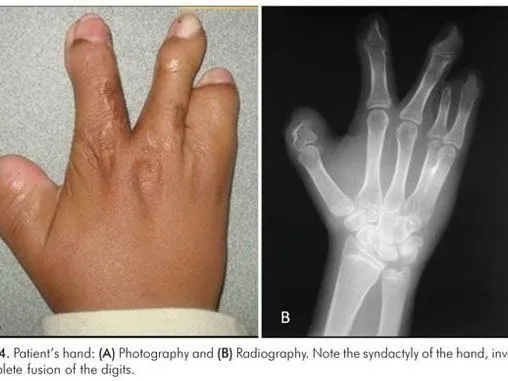

- Sindáctila: (unión de varios dedos) cutánea y ósea en las manos y en los pies que afectan, al menos, al segundo, tercer y cuarto dedo.